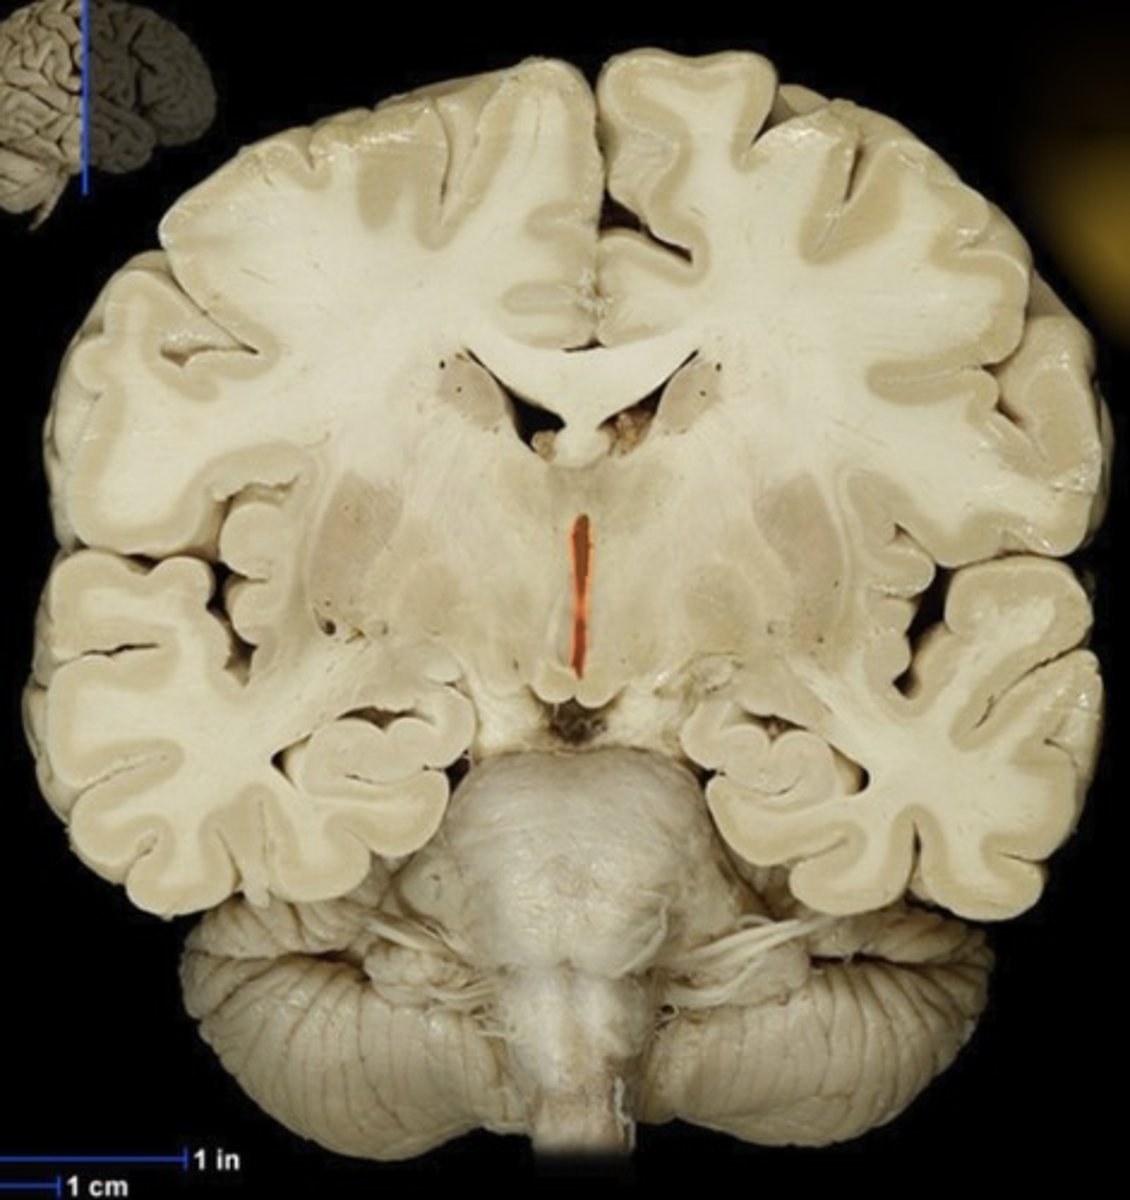

Gray matter (anterior view of coronal section)

Name this structure

White matter (anterior view of coronal section)

Name this structure

Corpus callosum

Name this structure

Fornix

Name this structure

Globus Pallidus

Name this structure

Hippocampus

Name this structure

Hypothalamus (anterior view of coronal section)

Name this structure

Lateral Ventricles

Name this structure

Mamillary body

Name this structure

Putamen

Name this structure

Thalamus (anterior view of coronal section)

Name this structure

Third Ventricle (anterior view of coronal section)

Name this structure

Cerebellum (anterior view of coronal section)

Name this structure